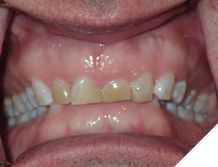

The majority of the orthodontic practices offer a period of “supervised retention” to their patients and communicates the customized retention recommendation with the patient’s general dentists. It is extremely important to work as a team to achieve long term clinical success in maintaining a functional bite and aesthetic smile. The general dentists continue to see their patients on a regular basis and have an opportunity to assess the orthodontic retainers and the bite after the supervised retention period is completed by the orthodontists. With great care, orthodontic retainers would serve for a long time (Fig. 1) without any major issues. However, in some cases, the failure to notice the clinical problems early on results in functional issues that would require a comprehensive orthodontic treatment to correct it (Fig. 2).

Fig. 2A

Fig. 2B

Fig. 2C